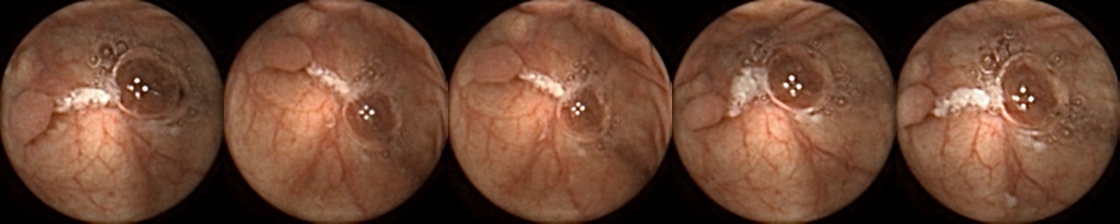

Similarly, we consider examples for the MIV model based on SimCLR pretraining using the pretrained ConvNext backbone in Figure 4. The model has a test accuracy of 86.26% for DBA L1 with 2 heads. Here we note again a similar trend by looking at the True Positive and False Negative examples as observed before, where a significant difference in the query image when compared with the target images can lead to a failure to identify the same polyp images in the five examples. A look at the False Positive examples affirms that the task remains challenging, as evidenced by the model’s occasional misclassifications in ambiguous cases.

True Positive False Negative

False Positive True Negative

Figure 4: True Positives (Pred = true, Label = true), False Negatives (Pred = false, Label = true), False Positives (Pred = true, Label = false),True Negatives (Pred = false, Label = false) for the DBA L1(h=2) model applying SimCLR using the ConvNeXt backbone. In each row, the leftmost image is the query and the 4 images to the right of each query are the target images.